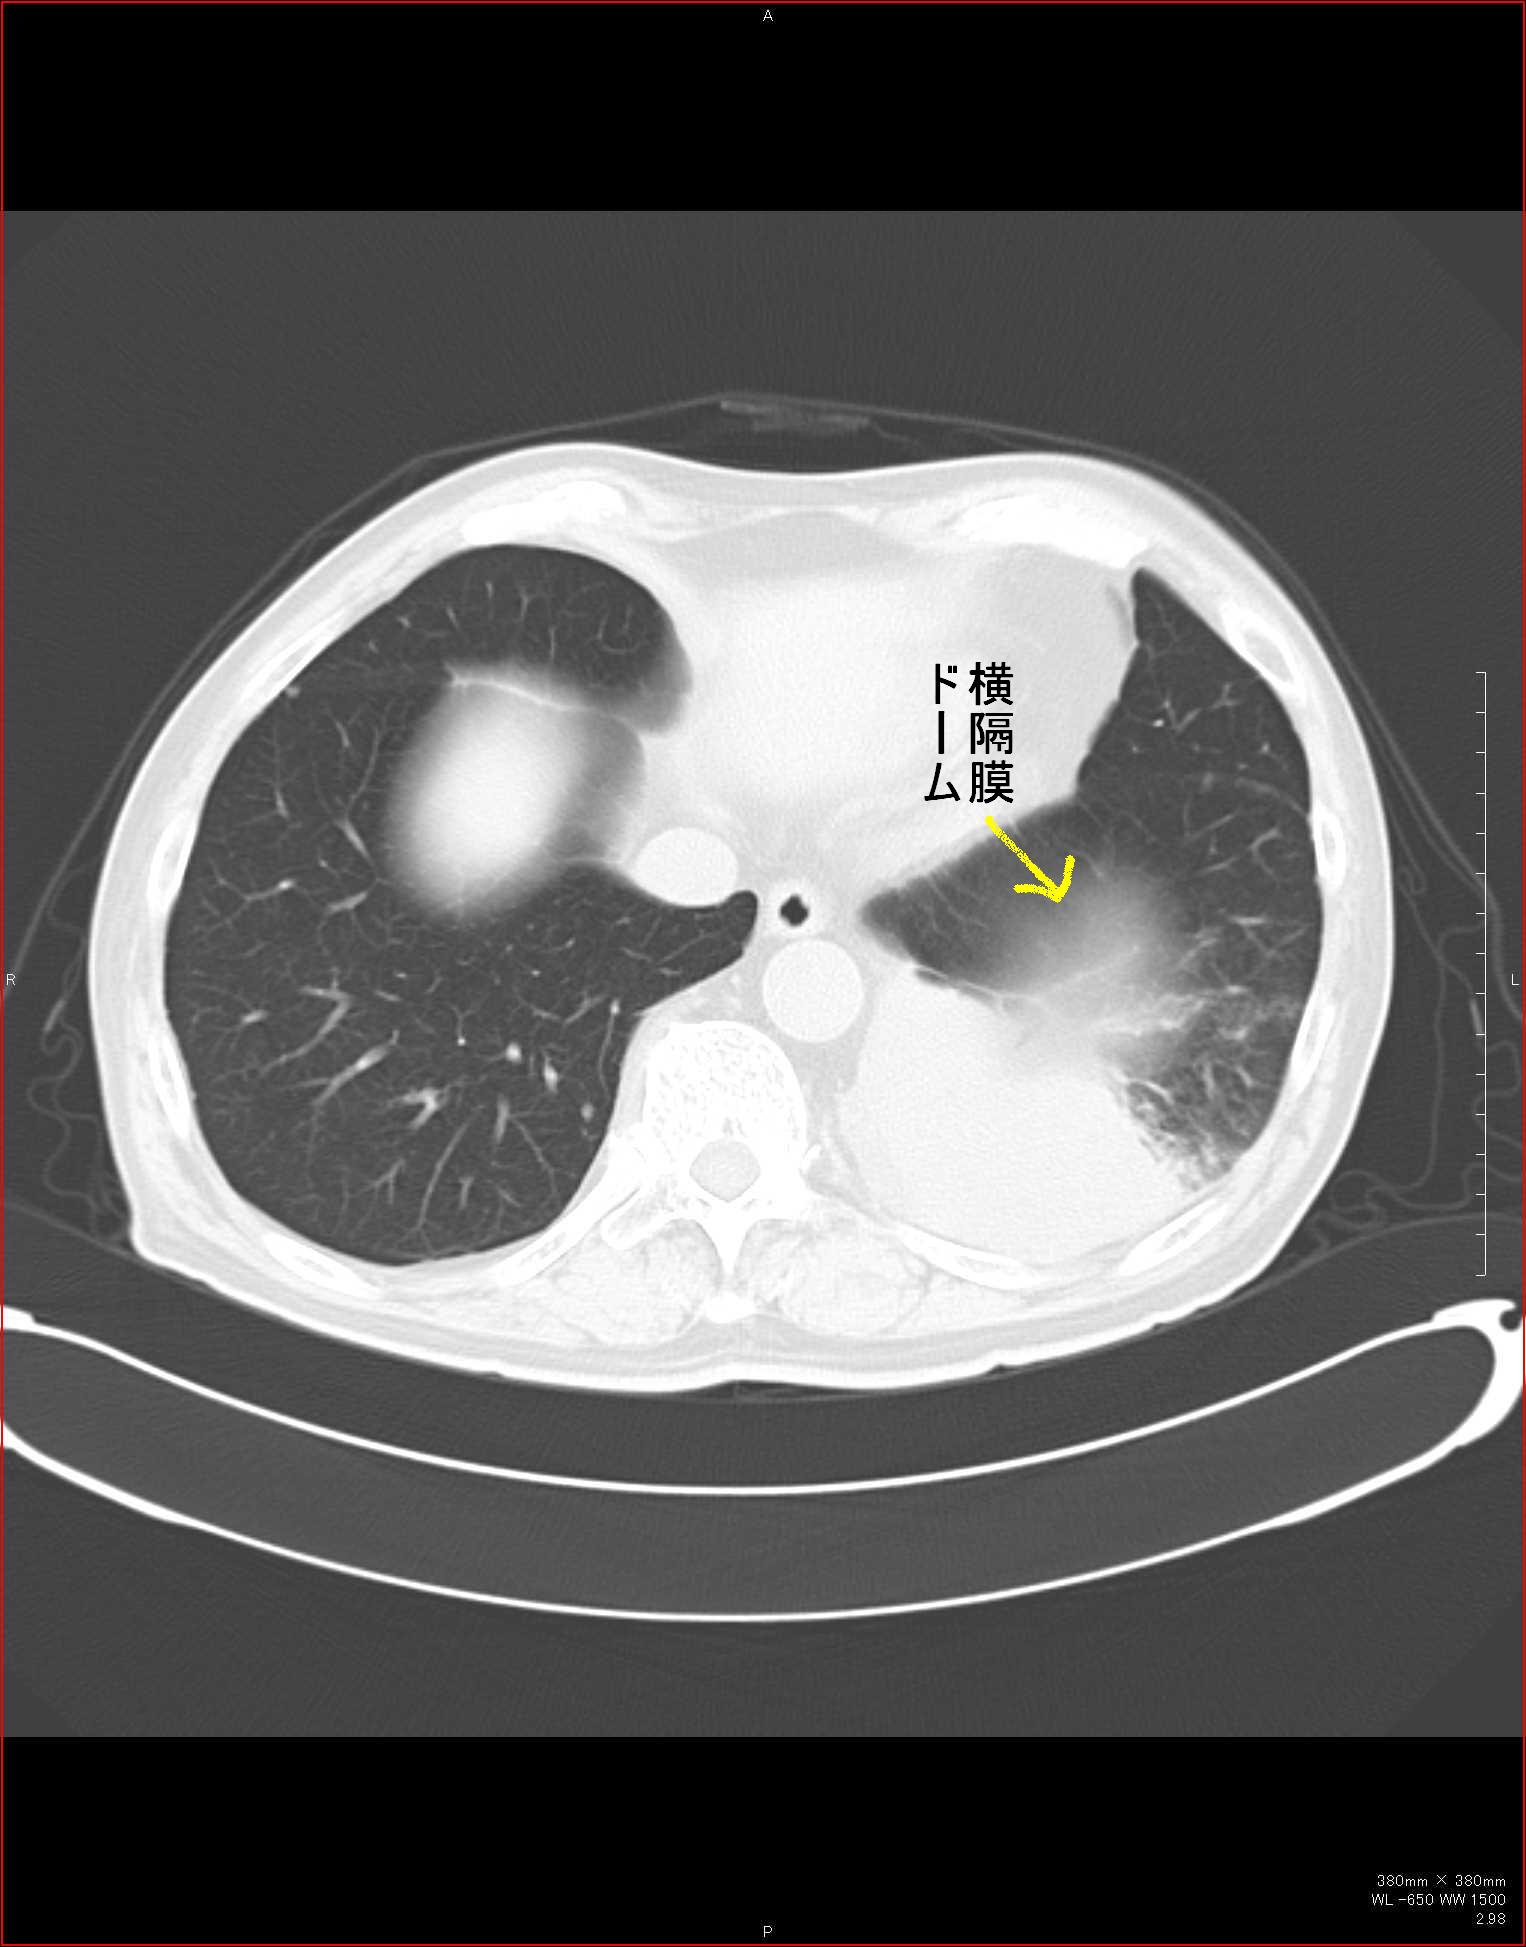

CTで見ると…

3Dだと、こうなります。

気管狭窄ですね。こういう所見もレントゲンで捉えることができるのです。